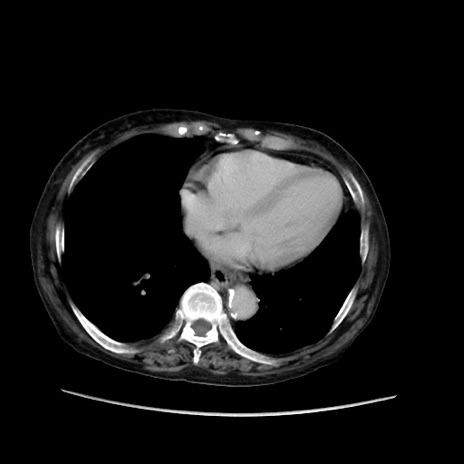

症例31(横断像)

【症例】80歳代 女性

【主訴】腹部膨満感

【現病歴】他院にて肝硬変にてフォロー中。1週間前から便秘、腹部膨満感、臍部腫瘤あり受診となる。

【既往歴】肝硬変

【身体所見】腹部膨隆あり、皮膚変化なし、疼痛なし。